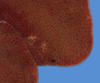

Tissue from 4 y.o. cat with SCC

What are the possible DDxs? What is the actual diagnosis?

DDxs: Reactive hyperplastic lymph node or metastasis of SCC

Actual diagnosis: reactive hyperplastic lymph node that is responding to a tumor